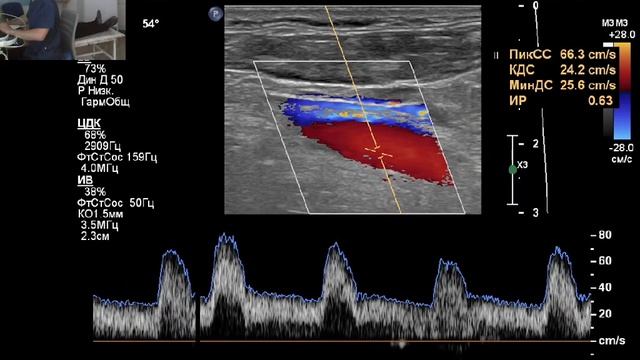

Видео узи артерий

Видео узи артерий 107 фото